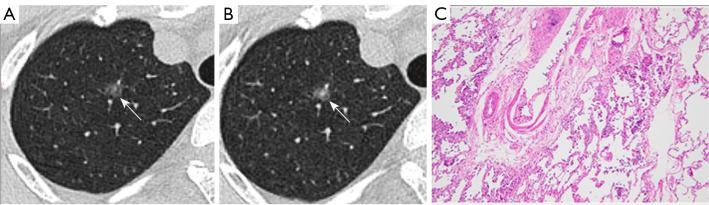

Different pathological stages of lung adenocarcinoma require different surgical strategies and have varying prognoses. Predicting their invasiveness is clinically important. This study aims to develop a nomogram to predict the invasiveness of lung adenocarcinoma manifesting as ground-glass nodules (GGNs) based on follow-up computed tomography (CT) imaging.

METHODS

We retrospectively collected data of 623 GGNs from 601 patients who underwent two follow-up chest CT scans and were confirmed as lung adenocarcinoma by postoperative pathology between June 2017 and August 2023. These patients were randomly divided into training and testing sets in a 7:3 ratio. Eighty-seven GGNs from 86 patients who underwent surgery between September 2023 and April 2024 were prospectively collected as a validation set. The volume, mean density, solid component volume (SV), percentage of solid component (PSC), and mass of GGNs were evaluated using the InferRead CT Lung software. Patients were classified into Group A (atypical adenomatous hyperplasia, adenocarcinoma in situ, and minimally invasive adenocarcinoma) and Group B (invasive adenocarcinoma). Three predictive models were established: model 1 utilized clinical characteristics and morphological features on pre-surgical CT, model 2 incorporated clinical characteristics, morphological features and quantitative parameters on pre-surgical CT, and model 3 utilized all selected features on baseline and pre-surgical CT.

肺腺癌的不同病理阶段需要不同的手术策略,且预后各异。预测其侵袭性在临床上具有重要意义。本研究旨在基于随访计算机断层扫描(CT)影像开发一种列线图,以预测表现为磨玻璃结节(GGN)的肺腺癌的侵袭性。

方法

我们回顾性收集了2017年6月至2023年8月期间601例接受两次胸部CT随访扫描且术后病理确诊为肺腺癌的患者的623个GGN数据。这些患者按7:3的比例随机分为训练集和测试集。前瞻性收集了2023年9月至2024年4月期间86例接受手术的患者的87个GGN作为验证集。使用InferRead CT Lung软件评估GGN的体积、平均密度、实性成分体积(SV)、实性成分百分比(PSC)和质量。患者分为A组(非典型腺瘤样增生、原位腺癌和微浸润腺癌)和B组(浸润性腺癌)。建立了三种预测模型:模型1利用术前CT的临床特征和形态学特征,模型2纳入术前CT的临床特征、形态学特征和定量参数,模型3利用基线和术前CT上所有选定的特征。